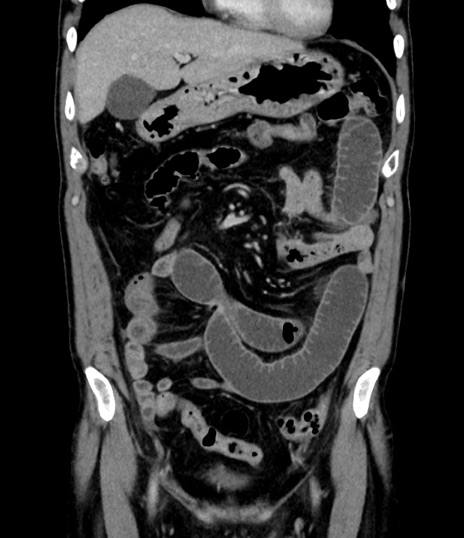

症例8(冠状断像)

【症例】 60歳代男性

【主訴】 黒色吐物

【現病歴】 4日前から嘔気自覚、2日前の朝食後にも嘔気あり、自分で手で嘔吐反射起こし嘔吐したところ血が混ざっていたため受診。

【既往歴】 5年前汎発性腹膜炎を伴う急性虫垂炎で手術、高血圧、前立腺肥大症、高脂血症

【身体所見】 腹部正中に手術癩痕あり 腹部平坦・軟圧痛なし膨満感あり

【データ】WBC 8400、CRP 4.54